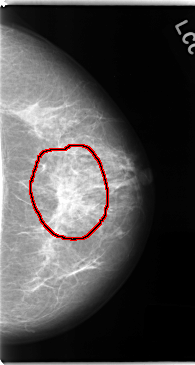

C_0137_1.LEFT_MLO

LEFT_MLO LINES 4736 PIXELS_PER_LINE 2680 BITS_PER_PIXEL 12 RESOLUTION 50 OVERLAY

FILE: C_0137_1.LEFT_MLO.OVERLAY

TOTAL_ABNORMALITIES 2

ABNORMALITY 1

LESION_TYPE MASS SHAPE ARCHITECTURAL_DISTORTION MARGINS SPICULATED

ASSESSMENT 5

SUBTLETY 5

PATHOLOGY MALIGNANT

TOTAL_OUTLINES 1

BOUNDARY

ABNORMALITY 2